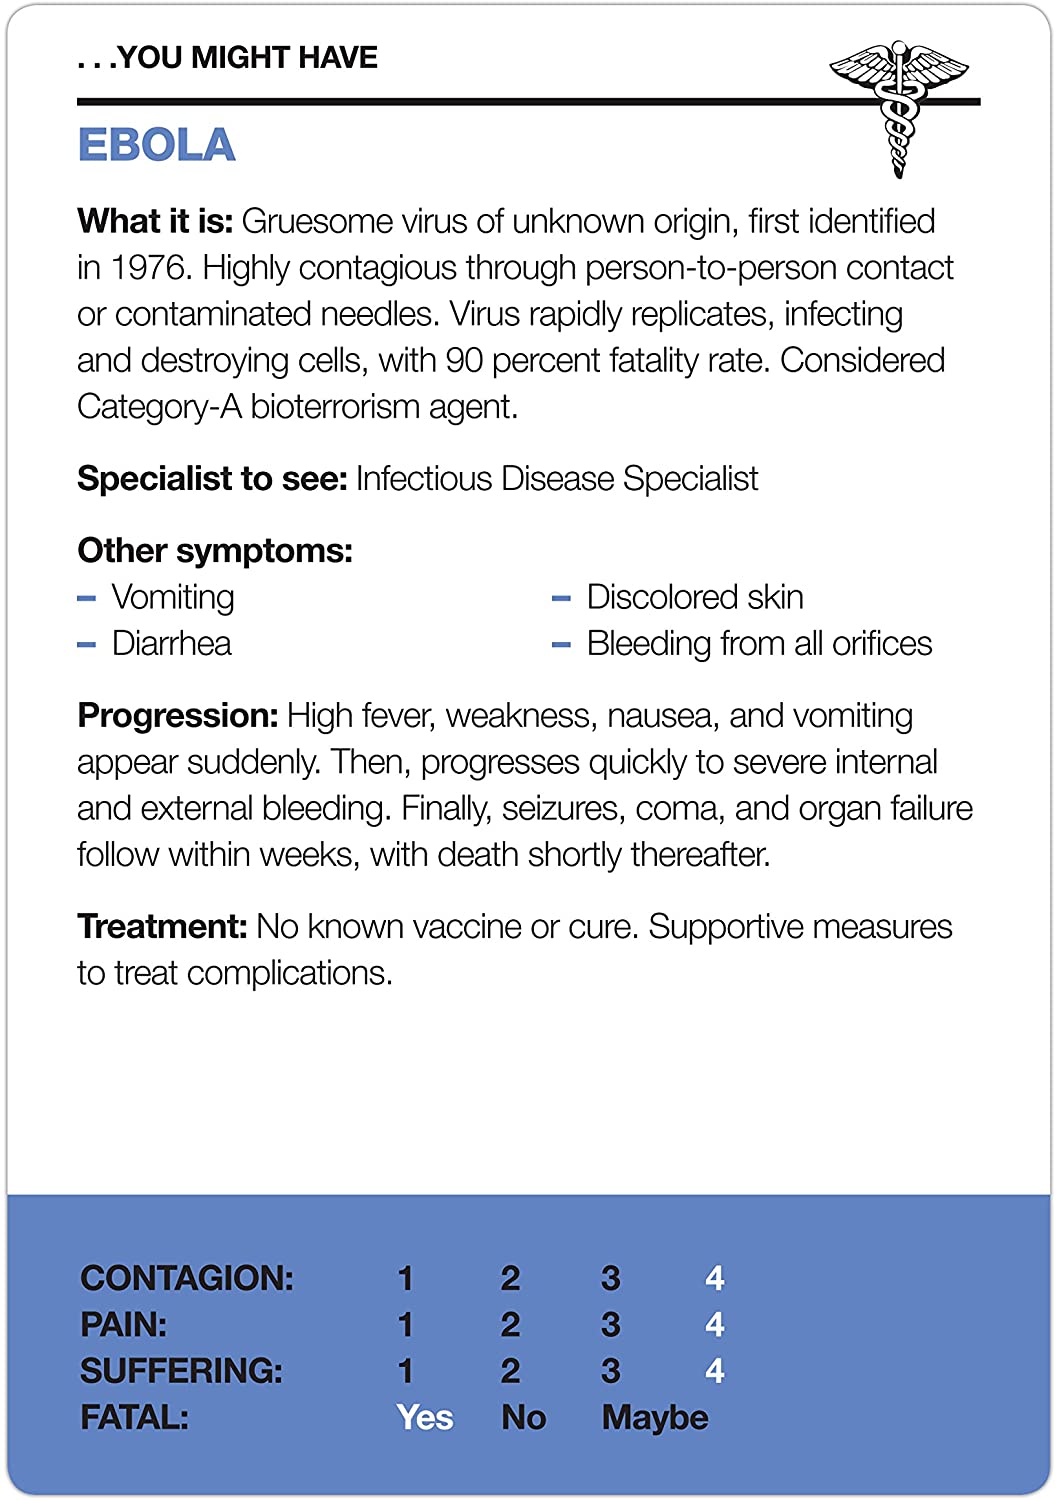

- With this deck of Fifty Things That Might Kill You, pick your symptom and pick a card (or cards) to see what rare, multisyllabic, and possibly fatal disease you might have

- A symptom checker that mixes dark humor (and actual facts) for hypochondriac fun!